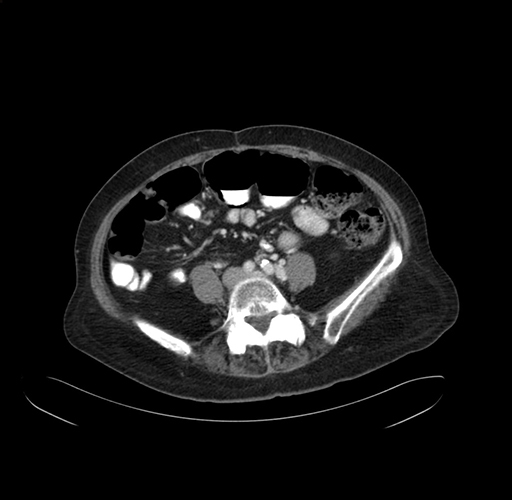

Axial Venous

Coronal Venous

Imaging analysis

Based on your CT findings, which issue(s) would give reason for "planned slowing down moment(s)" in this case?

Considering a standard right hepatectomy procedure, what step(s) of the operation would you do differently in this case?